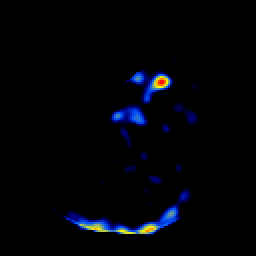

SPECT TL Study #3 -- Slice #16

[Home][Help][Clinical][Tour 1][Tour 2][Tour 3] Slice 16